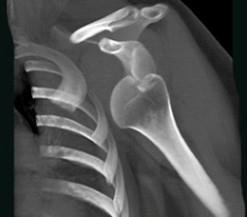

问题 男,18岁,肩部外伤,疼痛、活动受限,结合图像,最可能的诊断是 ( )

选项 A、肩锁关节脱位 B、肩关节未见脱位 C、肩关节喙突下脱位 D、肩关节锁骨下脱位 E、肩关节盂下脱位

答案 E